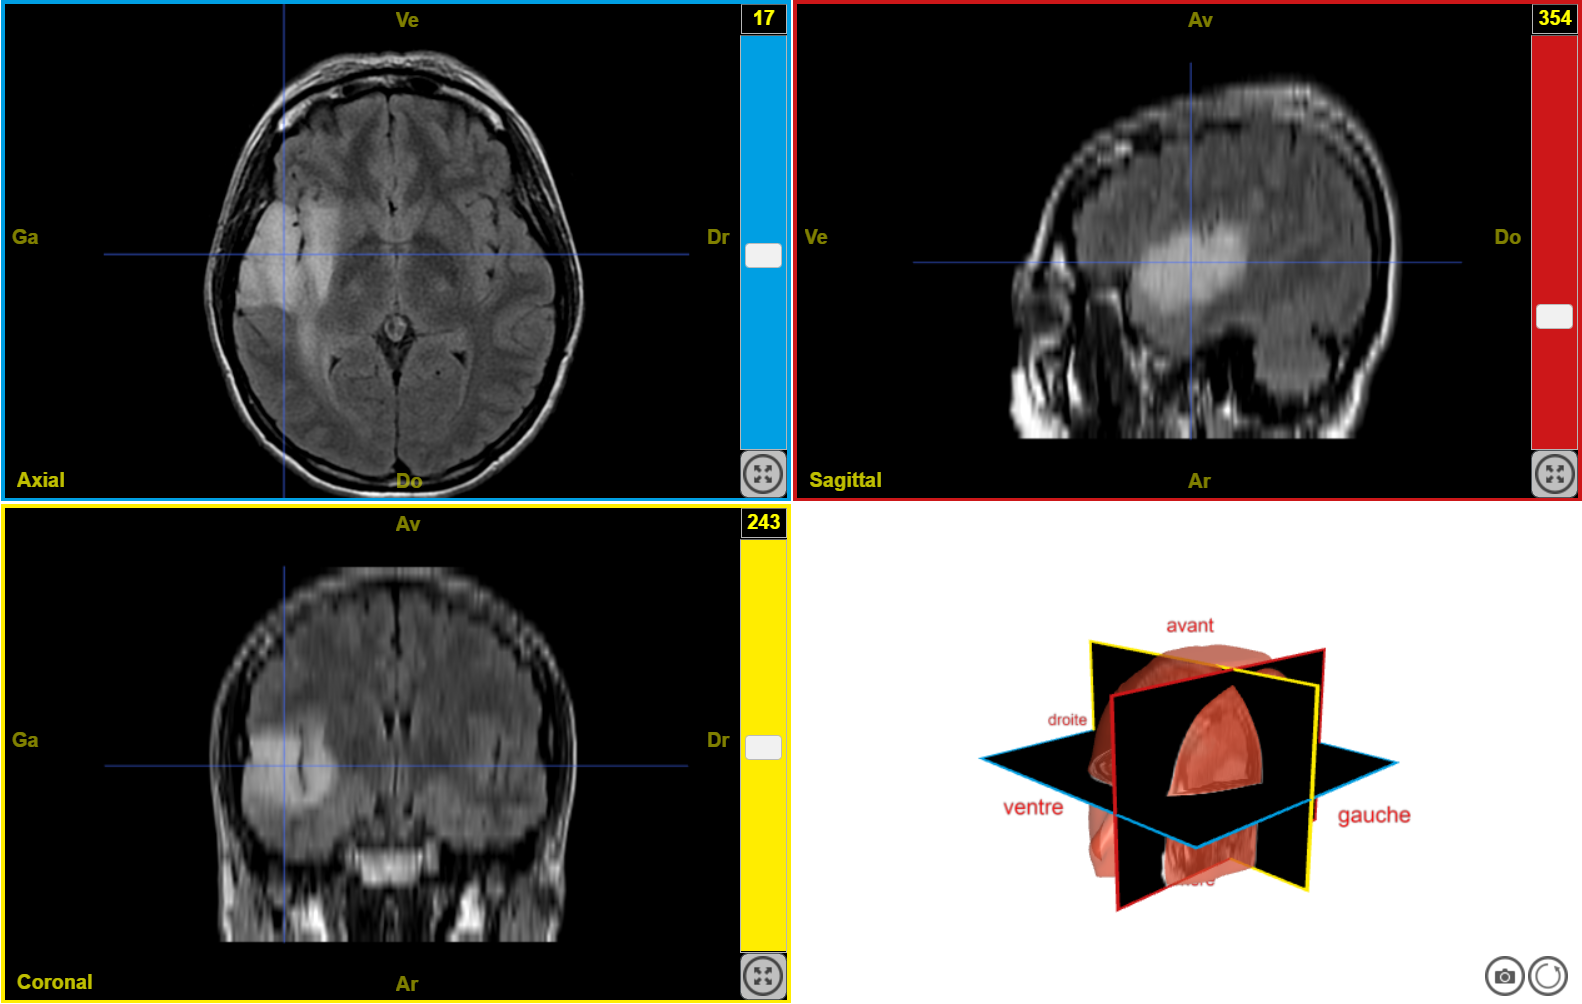

IRM tumeur T2 n1

Image dans sa taille originale :

408 ko